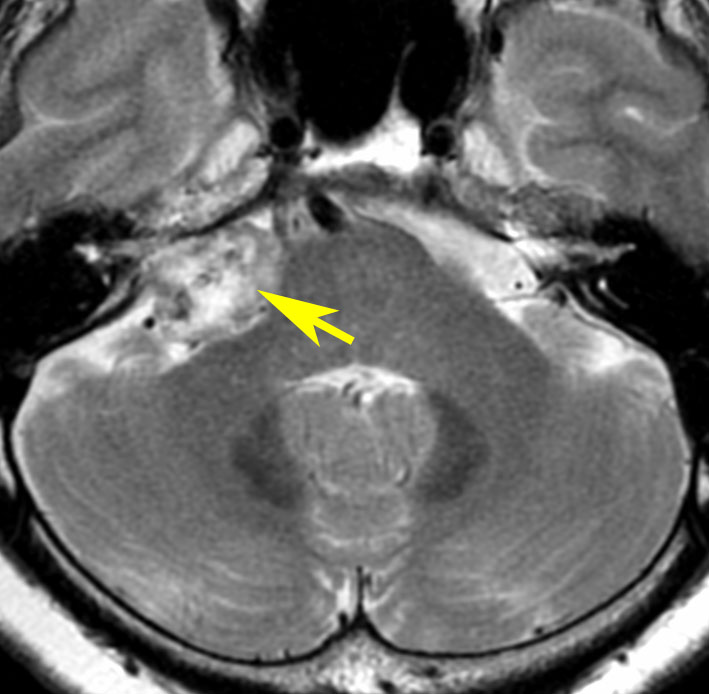

腫瘍が嚢胞性拡大で大きくなって,腫瘍内出血して,閉塞性水頭症になって意識障害を生じた患者さんです。このような事態になると臨時手術で腫瘍を摘出します。

大きなのう胞性聴神経腫瘍です。いくつかの袋が重なって腫瘍を形成しています。橋や延髄(脳幹部)が変形して,第4脳室がつぶれて閉塞しています。袋の周りが白く線状に造影されているのですが,この袋の壁だけに腫瘍細胞がありますから,これを剥がすように摘出します。顔面神経が薄くなって袋の壁にくっついているのですが,袋を破ってくしゃくしゃにすると顔面神経の位置が変わってしまって,顔面神経を損傷することがあるので要注意です。のう胞性聴神経腫瘍の方が顔面神経麻痺の後遺症の頻度が高いという報告もあるくらいです。この患者さんは迷走神経と舌咽神経の圧迫も強くて,ご飯を飲み込むことが難しくなっていました(嚥下障害)。

また,この患者さんは急に容態が悪くなって意識障害となりました。何故なら腫瘍の内部で出血したからです(黄色の矢印の部分)。第4脳室が詰まって閉塞性水頭症になって側脳室が拡大しています(右の画像)。